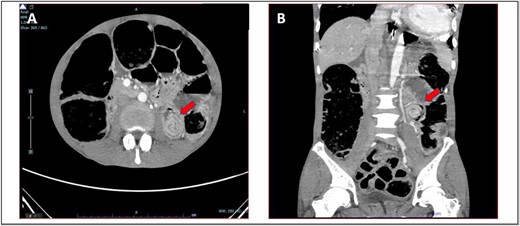

He presented with a history of abdominal distension for 1 week, loose stool, and vomiting for 3 days. Since admission to the ward, he had no bowel opening and did not pass flatus. On examination, he appeared dehydrated, and his abdomen was soft but distended. Plain abdominal radiograph showed dilated bowel. Computed tomography of the abdomen and pelvis showed short segment thickening of proximal transverse colon with dilatation bowel proximally, enlargement of mesenteric nodes, and mild ascites (Fig. 1). We proceeded with exploratory laparotomy, right hemicolectomy, and double barrel stoma. Intraoperatively, a noted tumour at proximal transverse colon size of about 5 × 4 cm with proximal bowel dilatation and distally bowel collapsed. Multiple mesocolic nodes were also present.

(A) Axial view and (B) coronal view of computed tomography showed short segment thickening of proximal transverse colon (red arrow) with dilatation of bowel.